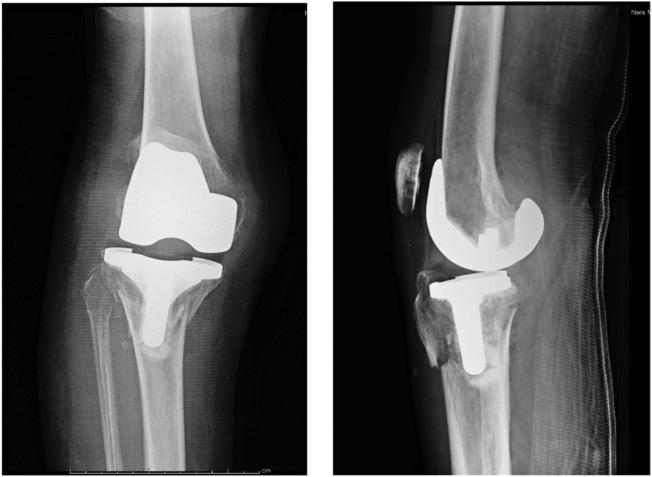

We present the case of a 79-year-old woman who presented at our center with a periprosthetic tibial fracture with a popliteal artery injury after total knee arthroplasty. Anastomosis of the popliteal artery was performed on the day of injury, and was later treated by open reduction and internal fixation. The patient was able to walk 3 months after injury. The present case was difficult to treat because of the arterial injury associated with periprosthetic fracture. Although revision of the implant was considered, open reduction and internal fixation was selected because of the severity of soft-tissue damage. The mechanism of injury is not uncommon, and it is expected that similar fractures will become more prevalent in the future as the number of knee replacement surgeries increases.

我们报告了一例79岁女性患者的病例,该患者在全膝关节置换术后因假体周围胫骨骨折合并腘动脉损伤前来我院就诊。受伤当天进行了腘动脉吻合术,随后接受了切开复位内固定治疗。患者受伤后3个月能够行走。由于假体周围骨折合并动脉损伤,本病例治疗困难。尽管考虑了翻修植入物,但由于软组织损伤严重,选择了切开复位内固定。这种损伤机制并不罕见,预计随着膝关节置换手术数量的增加,未来类似骨折将变得更加普遍。